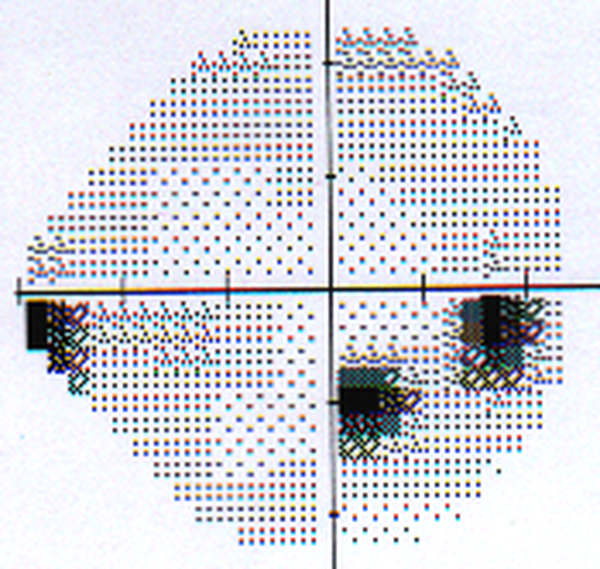

Progresjon av synsfeltskaden

(Klikk på bildet for å få det større) Samme pasient som over, men 5 år senere. Det er tilkommet et blindt område (såkalt skotom) nedenfor og til venstre for blind flekk. Dette kalles et begynnende Bjerrumskotom eller arkuat (bueformet) skotom. Det er her altså påvist progresjon av synsfeltskaden, men dette har tatt 5 år.  De fleste tilfeller med glaukom forverres meget langsomt.